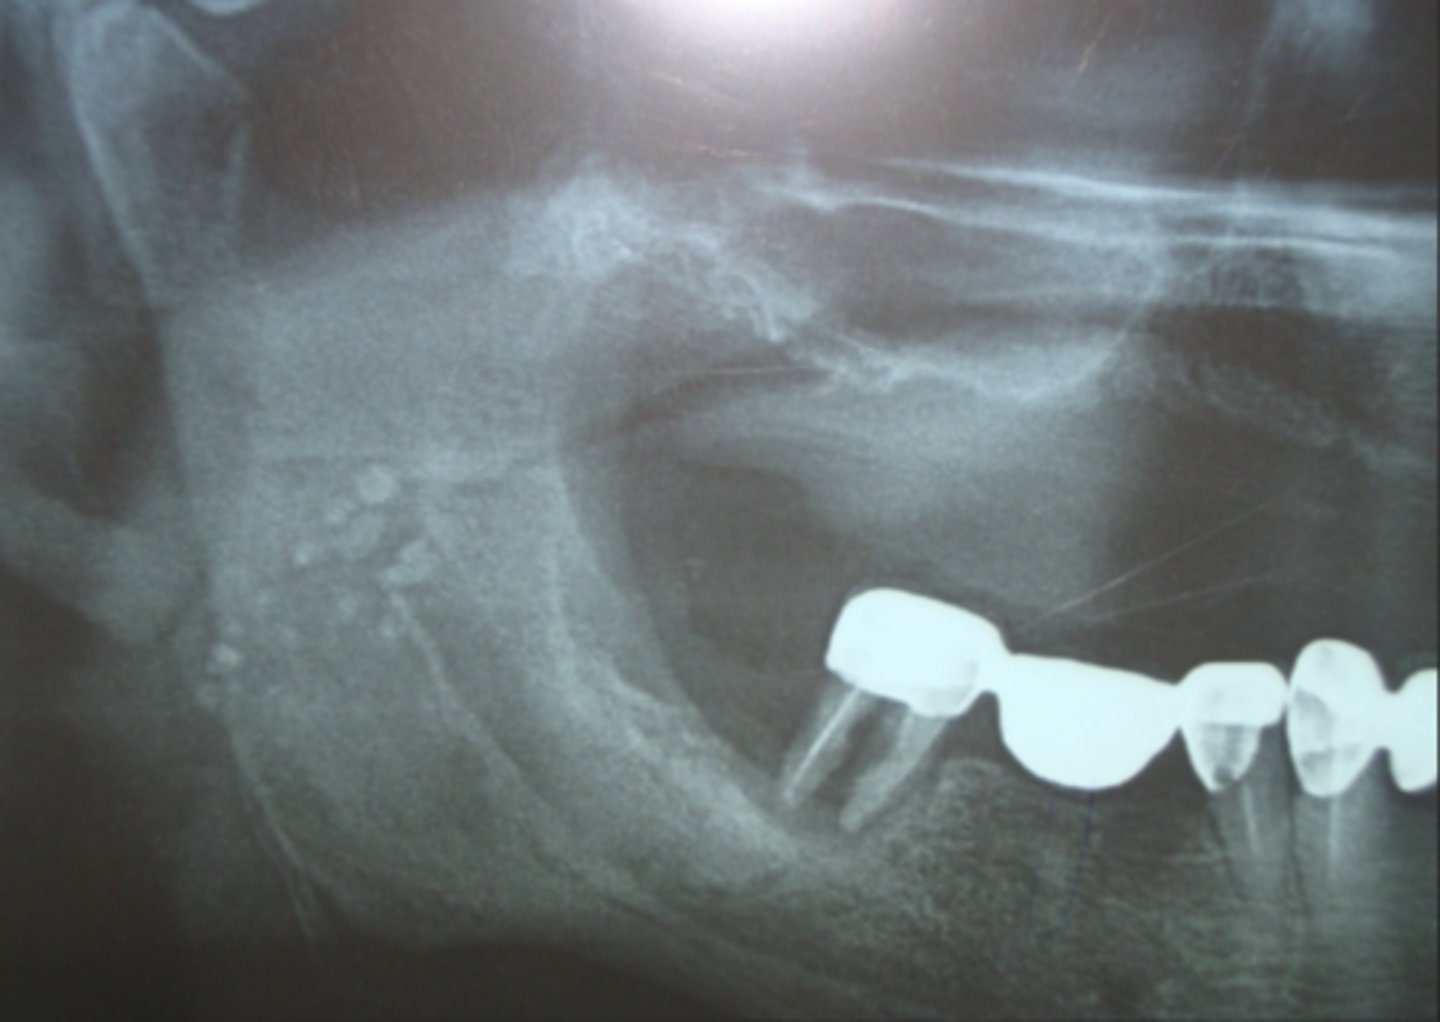

What are carotid artery calcifications?

Calcified atherosclerotic plaques in carotid artery

Where do carotid artery calcifications appear radiographically?

Near C3-C4 vertebrae

What should be done if you detect a carotid calcifications?

Refer pt to cardiology